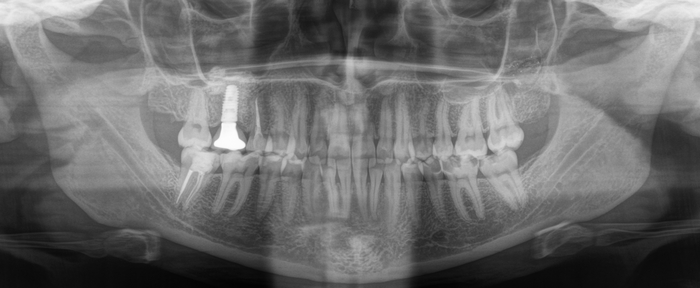

На панорамном снимке, сделанном после имплантации, хорошо видно, насколько высоко и неудачно она располагается:

Кстати, про этот клинический случай с имплантацией я рассказывал в этой статье.

Зуб, как мы выяснили, не самый приятный. Удалять его не особо-то и хотелось, поэтому я принял решение за ним понаблюдать и повторить снимок через год.

Вжух и год позади:

В целом, каких-то явных изменений нет. В подтверждение тому, что это не один и тот же снимок, вы можете обратить внимание, что на имплантате уже установлена постоянная коронка.